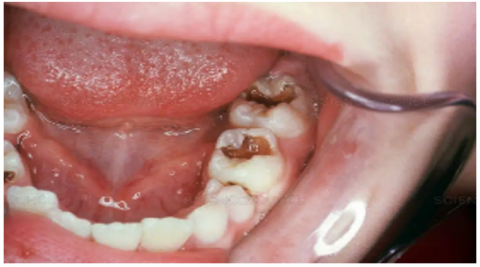

The dataset used in this study consists of 10,573 clinically sourced dental images, including contributions from publicly available repositories such as Kaggle. It provides a comprehensive foundation for training, validating, and testing the dental disease detection system [15]. The images are categorized into five distinct dental conditions: caries (2,382 images), gingivitis (2,349 images), hypodontia (1,251 images), mouth ulcers (2,541 images), and tooth discoloration (2,050 images) (Figure 1).

a

b

c

d

e

Figure 1. Dataset samples. (a) Caries, (b) Gingivitis, (c) Hypodontia, (d) Mouth ulcers, (e) Tooth discoloration

To facilitate the deep learning process, the dataset was partitioned into three subsets: 70% (7,399 images) for training, 15% (1,585 images) for validation, and 15% (1,589 images) for testing. Each subset was structured to maintain a balanced distribution of the categories to ensure fair training and evaluation [16].

The images, saved in JPEG format, were preprocessed to conform to an input shape of 224 × 224 pixels with three color channels (RGB). They represent clinical-grade dental photographs captured under varying angles and lighting conditions, enhancing the model's ability to generalize across diverse scenarios. This dataset serves as a robust resource for building a reliable and accurate system for automated dental disease detection.